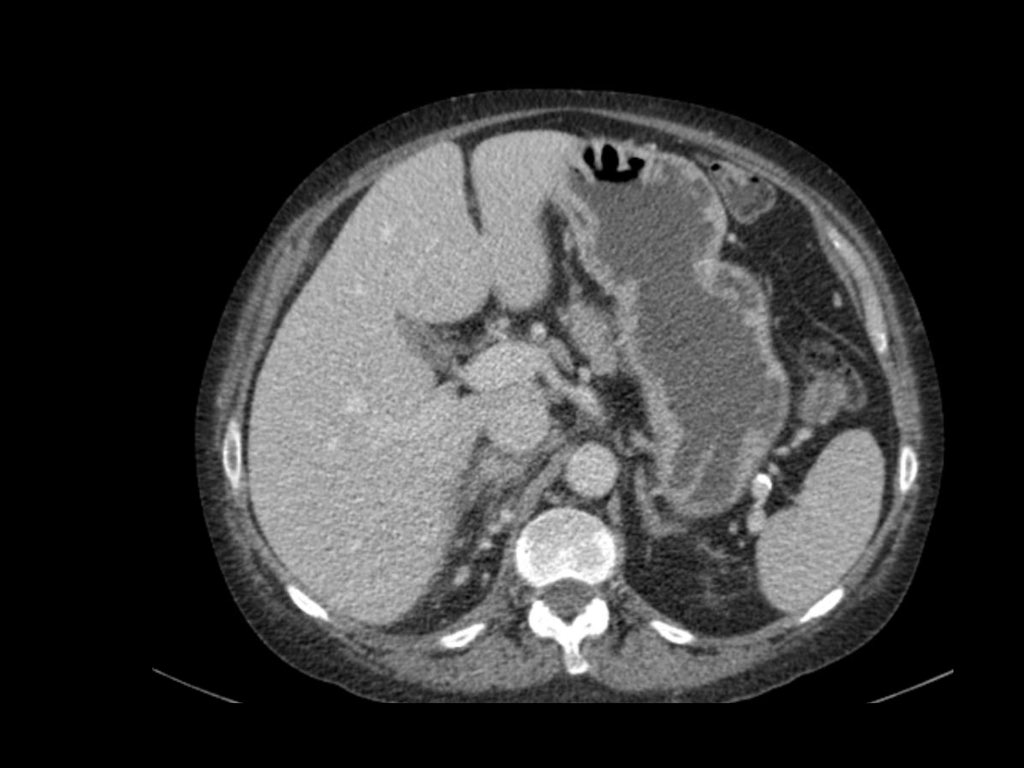

Đặc điểm điển hình của ung thư biểu mô tế bào sáng là ngấm thuốc mạnh trong thì vỏ-tủy (corticomedullary phase).

Điều này có thể khó đánh giá khi tổn thương nhỏ và nằm ở vỏ thận, vốn cũng ngấm thuốc mạnh.

Do đó, thì thận (nephrogenic phase) là thì nhạy cảm nhất để phát hiện các tổn thương này, vì nhu mô thận ngấm thuốc đồng nhất và đậm hơn so với khối u (hình minh họa).

Tổn thương thâm nhiễm ở cực trên thận phải, hầu như không thấy trên ảnh không tiêm thuốc (bên trái), thấy rõ ràng ở thì thận (bên phải). Giải phẫu bệnh xác nhận RCC tế bào sáng

Trong số tất cả các RCC tế bào sáng, khoảng 5% có kiểu tăng trưởng thâm nhiễm.

Mặc dù đây chỉ là một tỷ lệ nhỏ trong số các RCC, nhưng tần suất chung của RCC khiến đây trở thành một chẩn đoán phân biệt quan trọng đối với tổn thương thâm nhiễm dạng hình đậu (bean-type).

RCC thâm nhiễm có tính chất xâm lấn cao và tăng sinh mạch máu.

Tổn thương làm thay đổi cấu trúc nội tại của thận nhưng vẫn bảo tồn đường bờ thận. Các bất thường hệ thống đài bể thận có thể tương tự như những gì thấy trong ung thư biểu mô tế bào chuyển tiếp (transitional cell carcinoma).